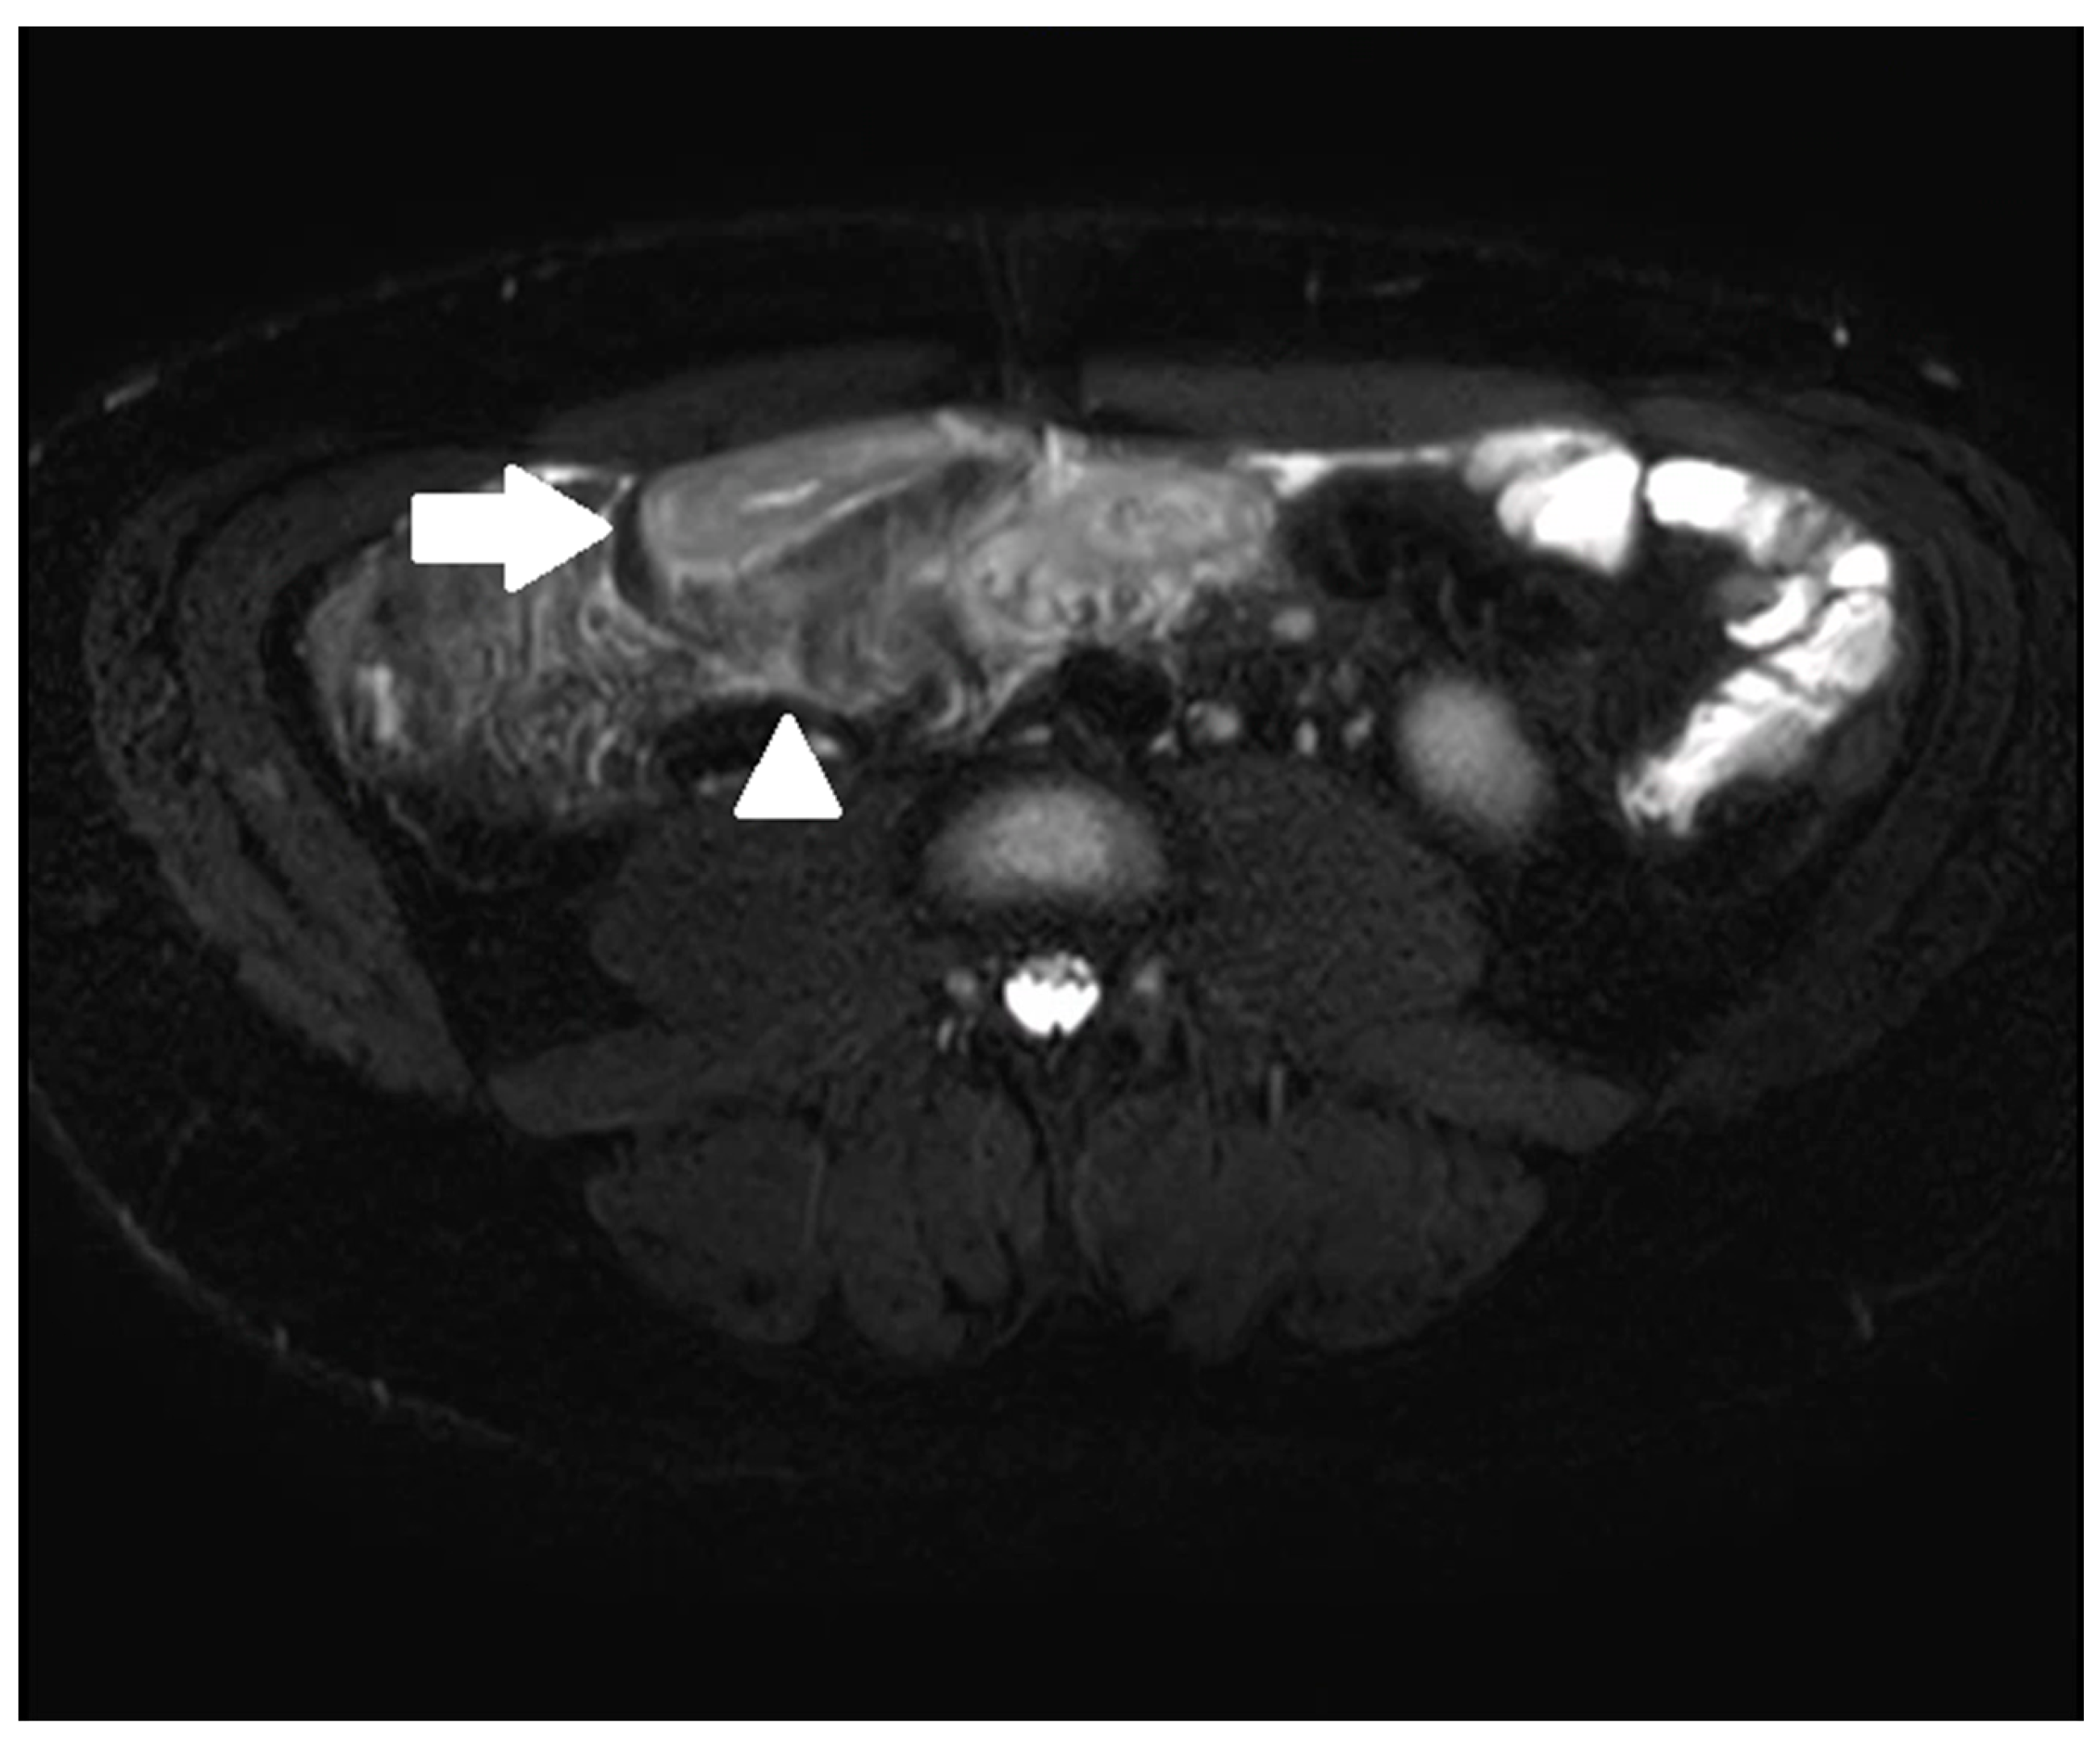

- Guglielmo, F.F.; Anupindi, S.A.; Fletcher, J.G.; Al-Hawary, M.M.; Dillman, J.R.; Grand, D.J.; Bruining, D.H.; Chatterji, M.; Darge, K.; Fidler, J.L.; et al. Small Bowel Crohn Disease at CT and MR Enterography: Imaging Atlas and Glossary of Terms. Radiographics 2020, 40, 354–375. [Google Scholar] [CrossRef] [PubMed]

- Sinha, R.; Verma, R.; Verma, S.; Rajesh, A. MR enterography of Crohn disease: Part 2, imaging and pathologic findings. AJR Am. J. Roentgenol. 2011, 197, 80–85. [Google Scholar] [CrossRef]

- Rimola, J.E. Cross-Sectional Imaging in Crohn’s Disease, 1st ed.; Springer International Publishing: Cham, Switzerland, 2019. [Google Scholar]